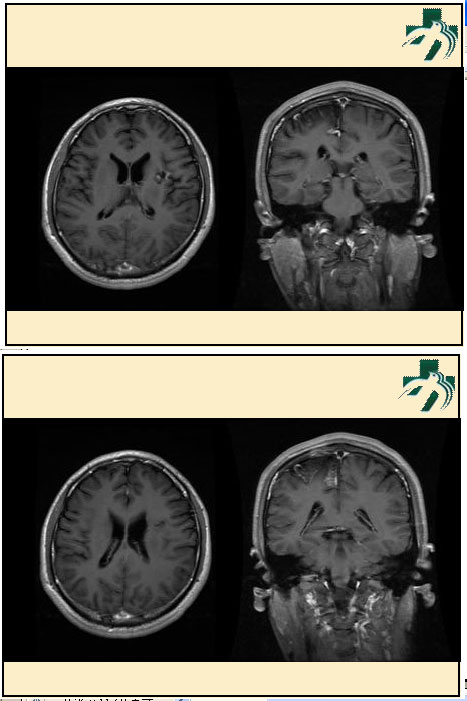

奴卡氏菌感染

第九期三博

读片会

病例之四

北京协和医院 提供

男性,22岁。自觉虫咬后皮疹、肢体麻木4月